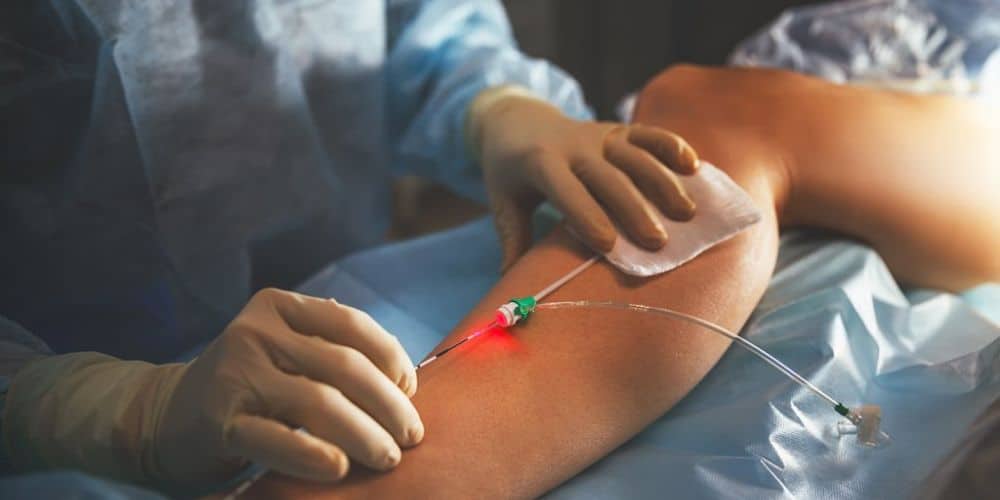

Entendiendo las Enfermedades Vasculares: Síntomas, Factores de Riesgo y TratamientoCirugía Vascular

Entendiendo las Enfermedades Vasculares: Síntomas, Factores de Riesgo y Tratamiento

Entendiendo las Enfermedades Vasculares: Síntomas, Factores de Riesgo y Tratamiento

Cirugía vascular: tipos, causas y tratamientoMedicina Estética admin3728octubre 28, 2024

Cirugía vascular: tipos, causas y tratamiento

Entendiendo las Enfermedades Vasculares: Síntomas, Factores de Riesgo y TratamientoCirugía Vascular admin3728marzo 26, 2025

Entendiendo las Enfermedades Vasculares: Síntomas, Factores de Riesgo y Tratamiento

Comprendiendo las Enfermedades Vasculares: Causas, Síntomas y Opciones de TratamientoCirugía Vascular admin3728diciembre 5, 2024

Comprendiendo las Enfermedades Vasculares: Causas, Síntomas y Opciones de Tratamiento